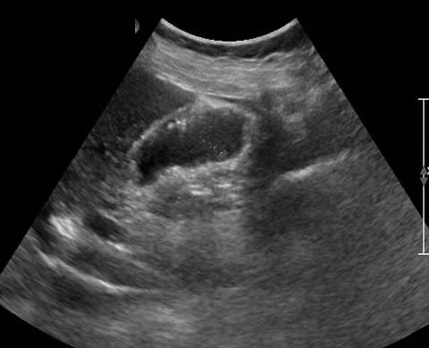

Image IRM de meme cas en pondere sur T2 :

Les sinus de Rokitansky-Aschoft sont hypersignal en

forme de collier au fond de la vesicule .. La

vesicule biliaire et sa contenue est tres

hyperintense |